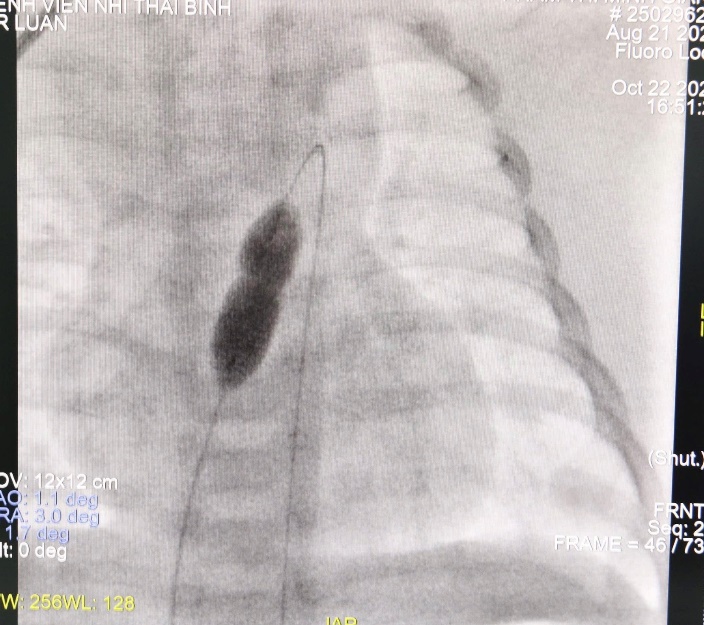

Hình ảnh trong quá trình can thiệp. Bóng nong được đưa vào và bơm căng để mở rộng van bị hẹp, giúp khôi phục dòng máu từ thất phải lên phổi.

Sau khi hội chẩn chuyên môn, các bác sĩ Khoa Tim mạch Bệnh viện Nhi Thái Bình đã chủ động triển khai kỹ thuật "Nong van động mạch phổi bằng bóng qua da", một kỹ thuật can thiệp tim bẩm sinh hiện đại, giúp mở rộng đường ra thất phải, cải thiện lưu thông máu mà không cần phẫu thuật mổ mở. Ca thủ thuật có sự tham gia giám sát và hỗ trợ về chuyên môn của TS. Lê Hồng Quang -Trung tâm Tim mạch, Bệnh viện Nhi Trung ương trong suốt quá trình thực hiện để đảm bảo an toàn tuyệt đối cho người bệnh.

Ca thủ thuật được thực hiện tại phòng can thiệp tim mạch với sự tham gia của các bác sĩ, kỹ thuật viên và điều dưỡng Khoa Tim mạch. Sau gần 90 phút, van động mạch phổi được mở rộng tốt, huyết động ổn định, không xảy ra biến chứng. Bệnh nhi hồi phục nhanh, bú tốt và hiện sức khỏe ổn định. Tại lần tái khám gần đây, các chỉ số tim mạch và hô hấp của trẻ đều trong giới hạn bình thường, sức khỏe tiến triển rất tốt.